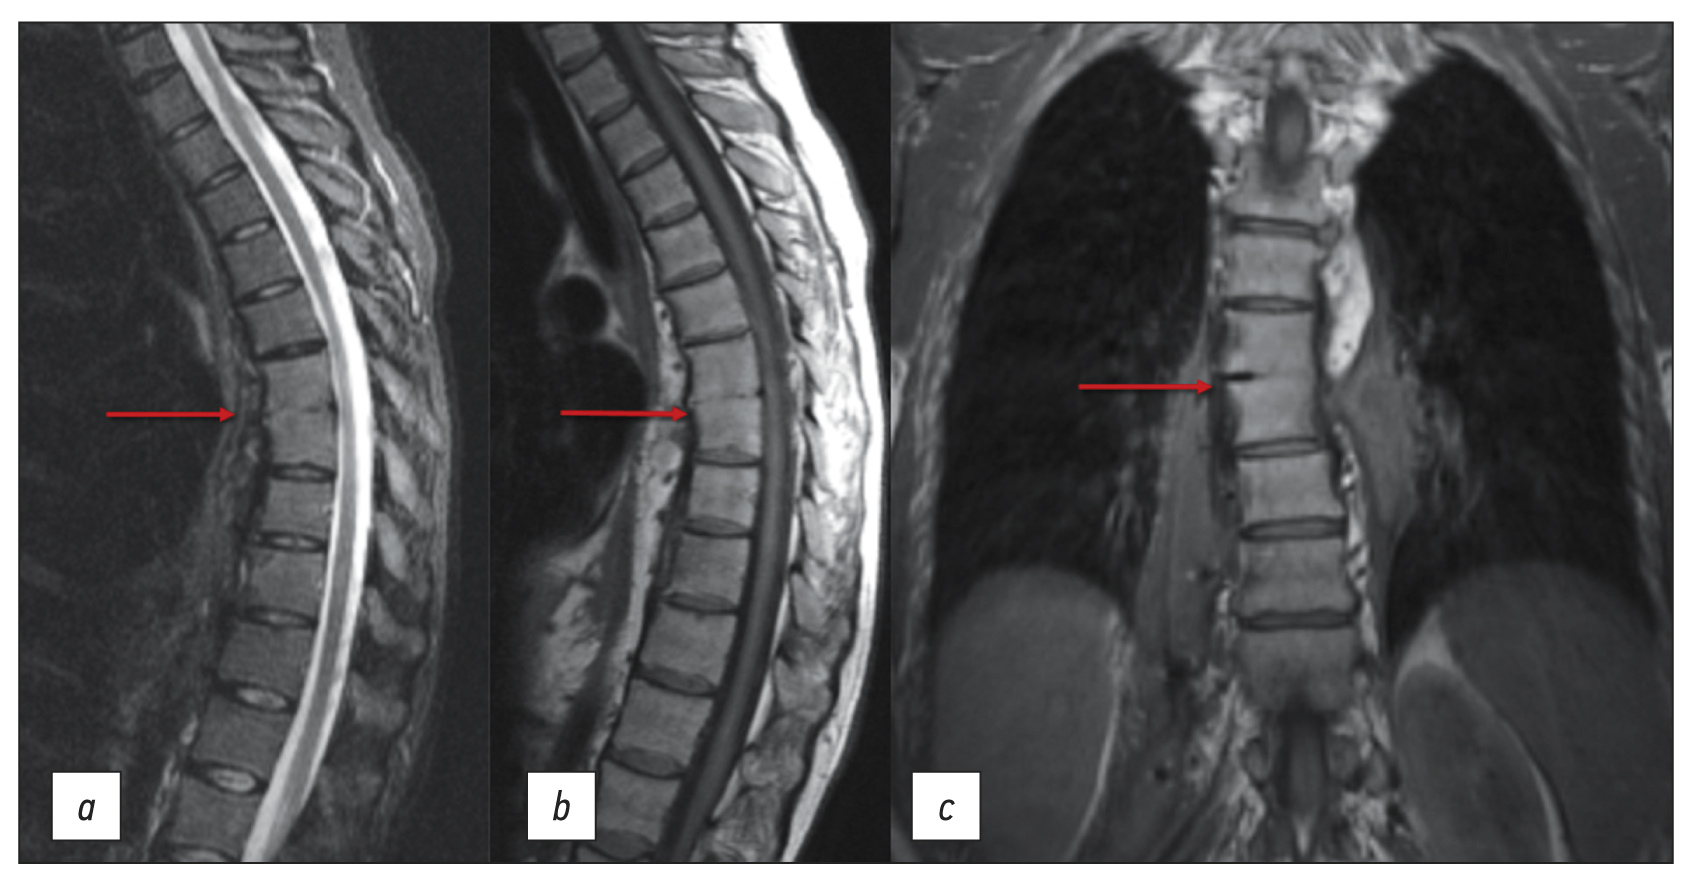

Chronic esophageal fistula as a rare cause of secondary osteomyelitis of the thoracic spine

Infectious diseases affecting the spine are inflammatory destructive diseases that involved the organ and its structural elements as a result of infection by hematogenic, lymphogenic, or contact pathways, including may be a complication of surgical intervention. In arriving at an accurate diagnosis, it is extremely important to evaluate the anamnesis, the clinical picture, as well as the data of laboratory studies and radiation diagnostics in the aggregate.

This article presents a clinical case with the development of secondary ThVII–ThVIII vertebral spondylitis due to esophageal fistula. At the initial diagnosis, spondylitis was associated with spinal anesthesia performed six months prior to onset of the disease, as there was a fistulous defect on the skin in the lumbar region. Consequently, surgical interventions were performed three times in a surgical hospital at the place of residence. The data from the endoscopic examination, as well as the patient’s complaints regarding the relationship between meals, the appearance of pain, and the nature of the discharge from the fistula were not taken into account by doctors initially. With the help of an additional examination, including computed tomography of the esophagus with oral contrast and computed tomography fistulography, the main diagnosis was esophageal fistula. Thoracic spondylitis was only a secondary complication.

Thus, the final diagnosis of back pain and fistula in the lumbar region should be formulated after differential diagnosis with alternative diseases of the spine.